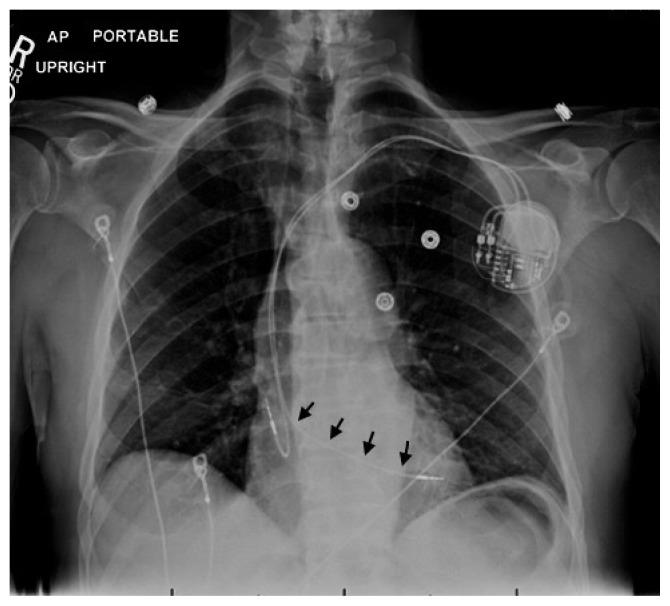

Incidental Detection of Inadvertent Pacing Lead Placement in the Left Ventricle by Myocardial Perfusion Imaging Study.